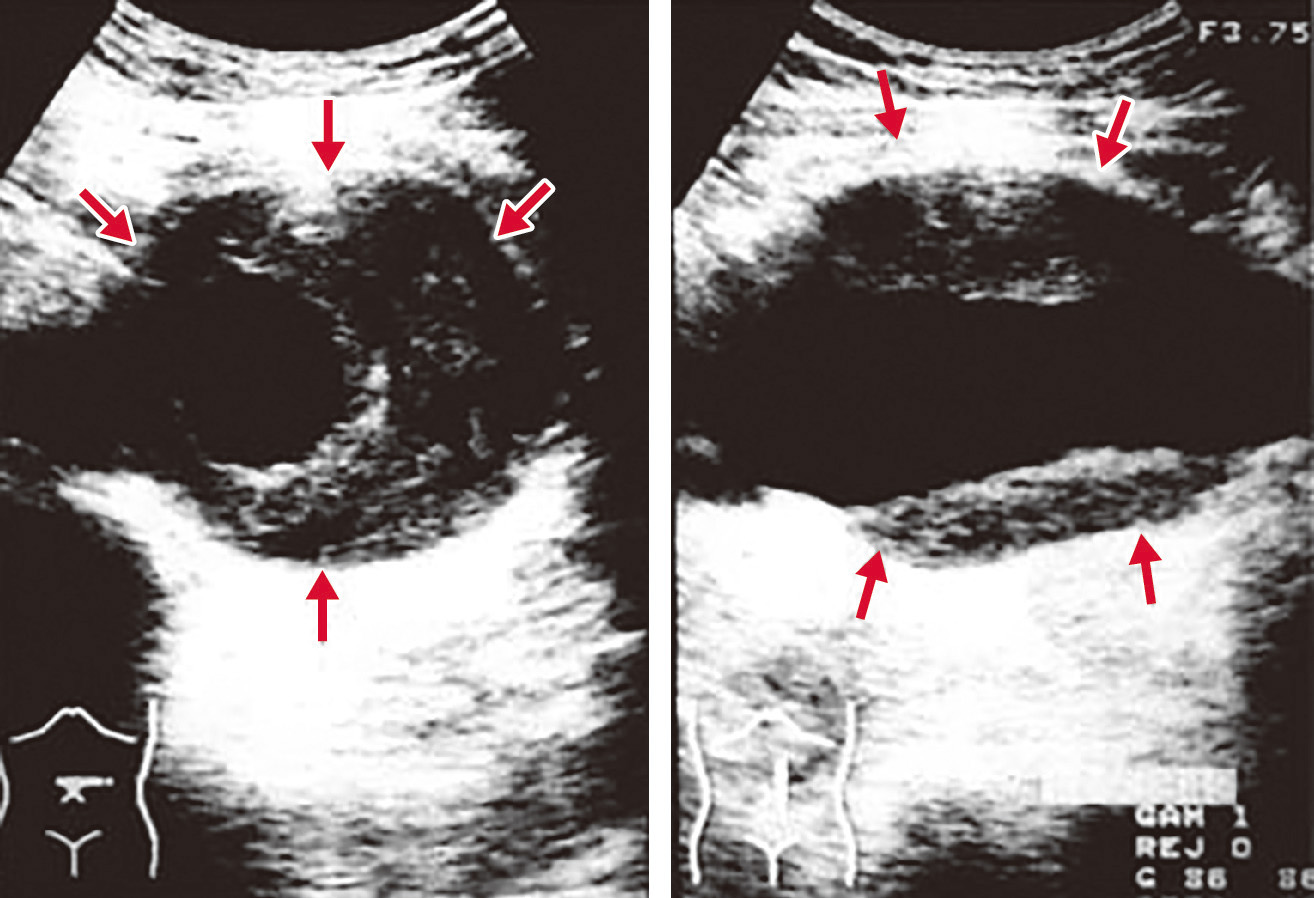

大動脈壁が脆弱化して局所的に全周性または一部が拡張した状態を大動脈瘤とよぶ.一般に,大動脈の外径の直径が正常部位の1.5倍 (目安として胸部大動脈系45 mm,腹部大動脈30 mm) をこえた状態を大動脈瘤と定義する.大部分は無症状のままに経過し,健診や医療機関受診の際の視診や触診,胸部X線写真正面像における縦隔拡大や側面像における拡大,腹部触診や腹部超音波 (図2) やCT (図3),MRI (図4) で発見され診断される.瘤の形状によって,紡錘状あるいは囊状,また壁構造の違いによって,瘤が内膜・中膜・外膜の3層すべてを有する真性動脈瘤と,中膜平滑筋層の連続性が失われ外膜や結合組織によって被包されている仮性大動脈瘤に分類される (図5).大動脈壁脆弱化の原因としては,外傷,梅毒,Marfan症候群などもあるが,最も大きな割合を占めるのは高血圧と加齢に伴う動脈硬化性変化であり,高齢男性に多い.大動脈瘤が解離したり破裂したりすると,激烈な胸背部痛や腹痛を訴えたり,血圧低下しショックに陥ったりする.いったんショック状態に陥った症例はもちろんのこと,病院に搬送されたとしても救命できる可能性は50%以下とされる.瘤径拡大スピードが高いほど,瘤形状が全体的でなく部分的であるほど,また当然,血圧が高いほど破裂リスクは高い.